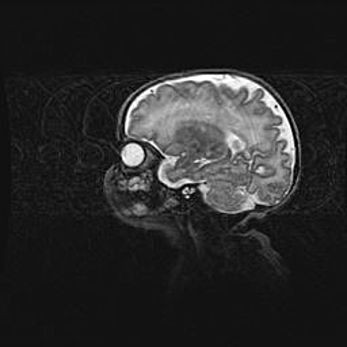

Мальформация Денди-Уокера. Киста задней черепной ямки.

Агенезия мозолистого тела.

Возраст: 2,5 месяца

Вес: 2420 г

Пол: женский

Окружность головы: 37 см

Срок гестации: 32 недели

Мальформация Денди—Уокера — редкий вид патологии ЦНС, представляющий собой врожденный порок развития каудального отдела ствола и червя мозжечка, ведущий к неполному раскрытию срединной (Мажанди) и латеральных (Лушка) апертур IV желудочка мозга. Для этогно синдрома характерна триада симптомов: гипотрофия червя мозжечка и/или полушарий мозжечка, кисты задней черепной ямки, гидроцефалия различной степени. В 70% случаев порок сочетается и с другими аномалиями головного мозга, в частности с агенезией мозолистого тела.